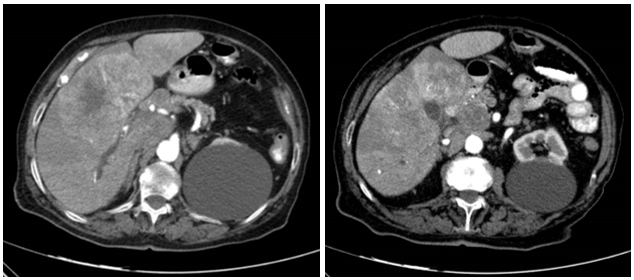

TAC abdominopélvico: lesión hepática de 10x7.5x8 cm en segmentos 4, 5 y 8 sugestiva de hepatocarcinoma, que condiciona ectasia distal de vía biliar intrahepática. Múltiples adenopatías en hilio hepático y espacio portocava con efecto masa sobre la cabeza pancreática, y paraaórticas anteriores e izquierdas supra e infrarrenales. Lesión mesentérica de 2x1.5 cm en bifurcación aortica compatible con lesión secundaria.

Ante los hallazgos ecográficos, Radiodiagnóstico amplía el estudio con TAC abdominopélvico. Ante resultados, derivamos a Cirugía General quienes desestiman tratamiento quirúrgico o ablativo locorregional y remiten a Oncología, quienes ante la extensión desestiman la realización de más pruebas y/o tratamiento con finalidad curativa; recomendando valoración por Cuidados Paliativos.